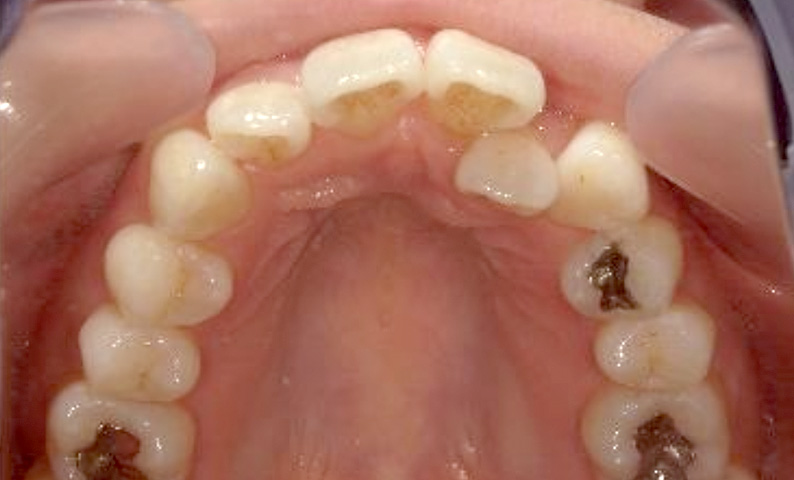

症例_018 上顎だけの部分矯正

治療期間:7ヶ月金額:30万円+税女性前歯のガタガタ上の前歯だけ

| Before | After |

|---|---|

|